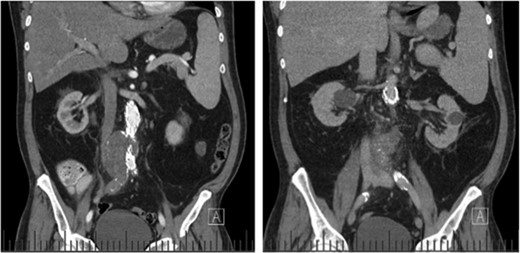

Computed tomography (CT) angiography revealed increased aortic size compared with a scan 1-month prior (5.4 cm compared with 5.0 cm) with diffuse peri-aortic inflammation. The findings implied an infected endograft (Figs 1 and 2).

Sagittal CT images indicating enlarged aneurysm sac (left) and para-aortic fat stranding (right) representing periaortitis.